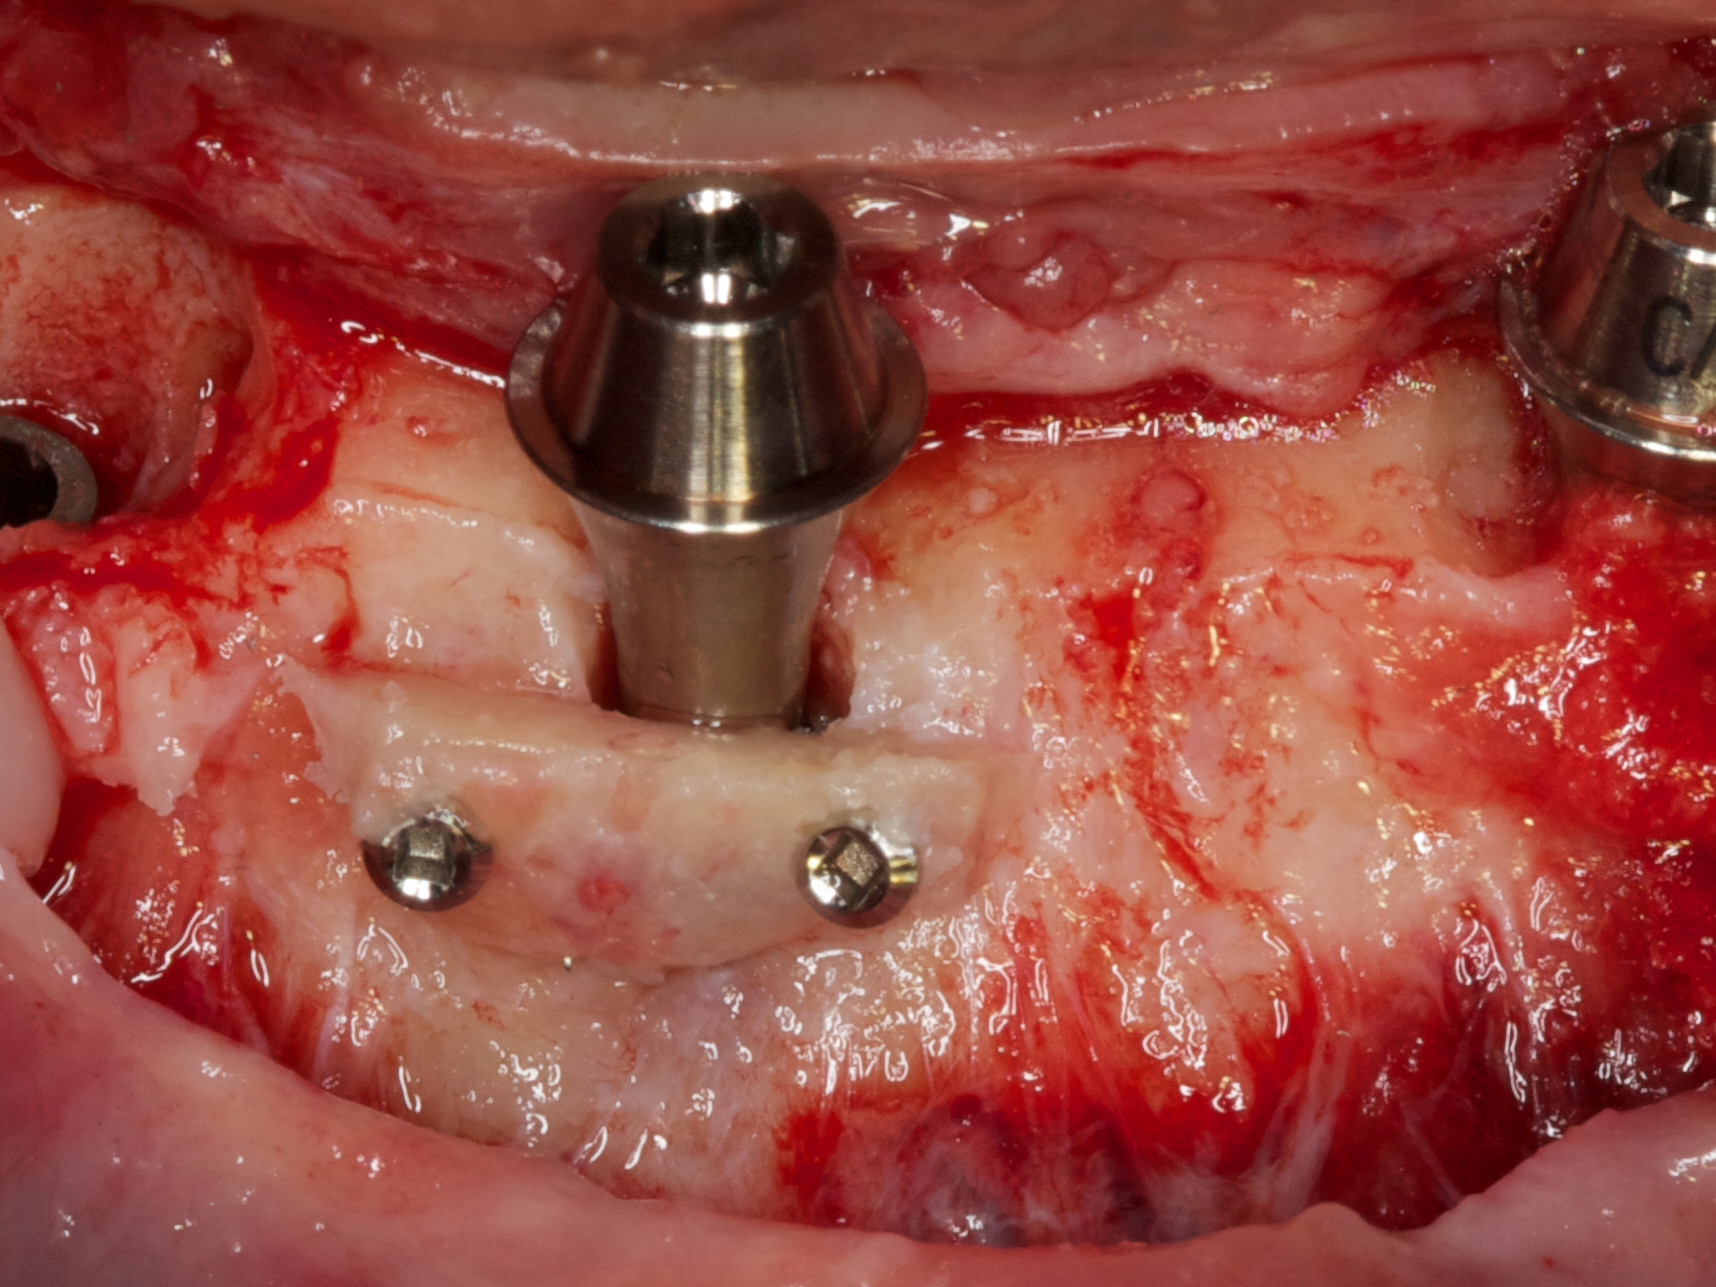

Für die Allgemeinanästhesie erfolgte zunächst die zusätzliche Gabe eines typischen Infiltrationsanästhetikums. Intravenös wurde unmittelbar präoperativ das Antibiotikum Clindamycin 600 mg gegeben. Abbildung 7 zeigt die klinische Ausgangssituation linksseitig. Nach der vorsichtigen Durchtrennung der Brückenkonstruktion (Abb. 8) jeweils vor der Krone auf den Blattimplantaten und Entfernung der nicht erhaltungswürdigen Zähne 44 bis 33 samt ihrer Überkronung (Abb. 9) wurde der Mukoperiostlappen vestibulär wie lingual passend zur erstellten Schablone präpariert und die Bohrschablone in ihrer finalen Lage eingebracht (Abb. 10). Zunächst erfolgte die Insertion der angulierten Implantate Ankylos ® C/X-Implantate (Durchmesser 3,5 mm) der Länge 14 mm in regio 034 (Abb. 11 und 12) und 044. Danach wurden in den Positionen 032 und 042 jeweils ein weiteres Ankylos ® C/X –A-Implantat mit gleicher Länge und Durchmesser inseriert (Abb. 13). Sämtliche entfernten Knochenpartikel und auch Bohrspäne wurden akribisch asserviert. In den Positionen 032 und 042 wurden Ankylos ® Balance Basisaufbauten C/ (GH 3,0 / Ø 5,5 mm, Kopfhöhe 2,4 mm) mit 15 N/cm eingeschraubt. Anschließend hat der Zahntechniker mittels der Ankylos ® Modellierhilfskappenfür den Balance Basisaufbau Retentionskappen hergestellt, die mit 25 N/cm eingebracht wurden (Abb. 14). Am Implantat regio 042 wurde der Knochen in Schalentechnik nach vestibulär aufgebaut (Abb. 15)⁹,¹⁰. Im nächsten Schritt haben wir die angulierten Ankylos ® Balance Basisaufbauten C (nicht indexierte Abutments) in Regio 034 und 044 (GH 3,0, A30 / Ø 4,2 mm, Kopfhöhe 1,3 mm) ausgerichtet und ihren spezifischen Vorgaben entsprechend eingebracht (Abb. 16). Nachdem sich alle erforderlichen prothetischen Implantatbauteile in situ befanden (Abb. 17), erfolgte die Überprüfung und geringfügige Anpassung des im Vorfeld digital erstellten Sofortprovisoriums. Im Anschluss wurden die leeren Alveolen und Knochendefekte mit dem gewonnenen autologen partikulären Material aufgefüllt. Dann erfolgte der typische Naht-Wund-Verschluss mit Einzelknopfnähten eines resorbierbaren Nahtmaterials (Abb. 18). Nachdem die Patientin aus der Vollnarkose erwacht war und ihre motorischen Fähigkeiten wiedererlangt hatte, wurde das Sofortprovisorium eingesetzt und in Okklusion gebracht. In dieser Position wurden die Retentionskappen über ein selbsthärtendes fluoreszierendes kaltpolymerisierendes Paste-Kartuschensystem fixiert. Anschließend erfolgte die extraorale Versäuberung des Interimszahnersatzes. Nach Refixierung des Sofortprovisoriums in der Mundhöhle (Abb. 19 und 20) und dem Verschluss der Schraubenkanäle mit Kunststoff erfolgte die radiologische Kontrolluntersuchung (Abb. 21).